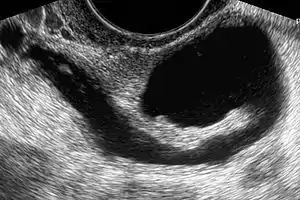

Gynecologic ultrasonography or gynecologic sonography refers to the application of medical ultrasonography to the female pelvic organs (specifically the uterus, the ovaries, and the fallopian tubes) as well as the bladder, the adnexa, and the recto-uterine pouch. The procedure may lead to other medically relevant findings in the pelvis.This technique is useful to detect myomas or mullerian malformations.

The examination can be performed by transabdominal ultrasonography, generally with a full bladder which acts as an acoustic window to achieve better visualization of pelvis organs, or by transvaginal ultrasonography with a specifically designed vaginal transducer. Transvaginal imaging utilizes a higher frequency imaging, which gives better resolution of the ovaries, uterus and endometrium (the fallopian tubes are generally not seen unless distended), but is limited to depth of image penetration, whereas larger lesions reaching into the abdomen are better seen transabdominally. Having a full bladder for the transabdominal portion of the exam is helpful because sound travels through fluid with less attenuation to better visualize the uterus and ovaries which lies posteriorly to the bladder. The procedure is by definition invasive when performed transvaginally. Scans are performed by health care professionals called sonographers, or gynecologists trained in ultrasound.

- to diagnose and manage gynecologic problems including endometriosis, leiomyoma, adenomyosis, ovarian cysts and lesions,

- to identify adnexal masses, including ectopic pregnancy,

Through transvaginal sonography ovarian cysts can be aspirated. This technique is also used in transvaginal oocyte retrieval to obtain human eggs (oocytes) through sonographic directed transvaginal puncture of ovarian follicles in IVF.